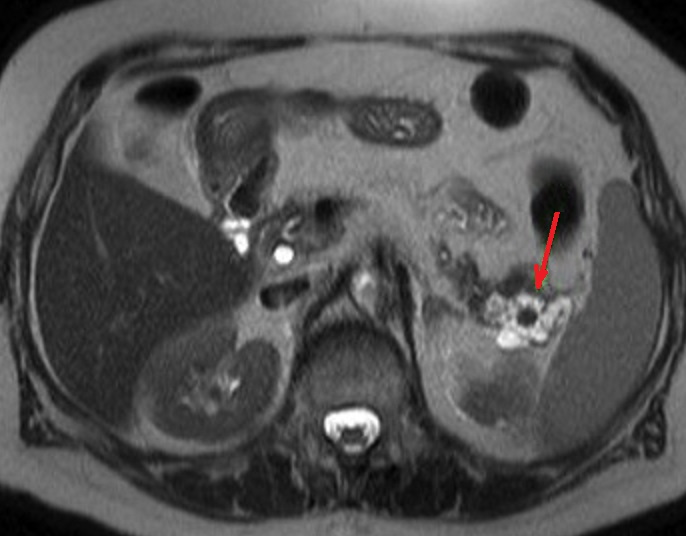

Image radiologique IRM d'un

pancreas( fleche rouge ) .Image radiologique IRM

ponderee T2 coupe axiale |